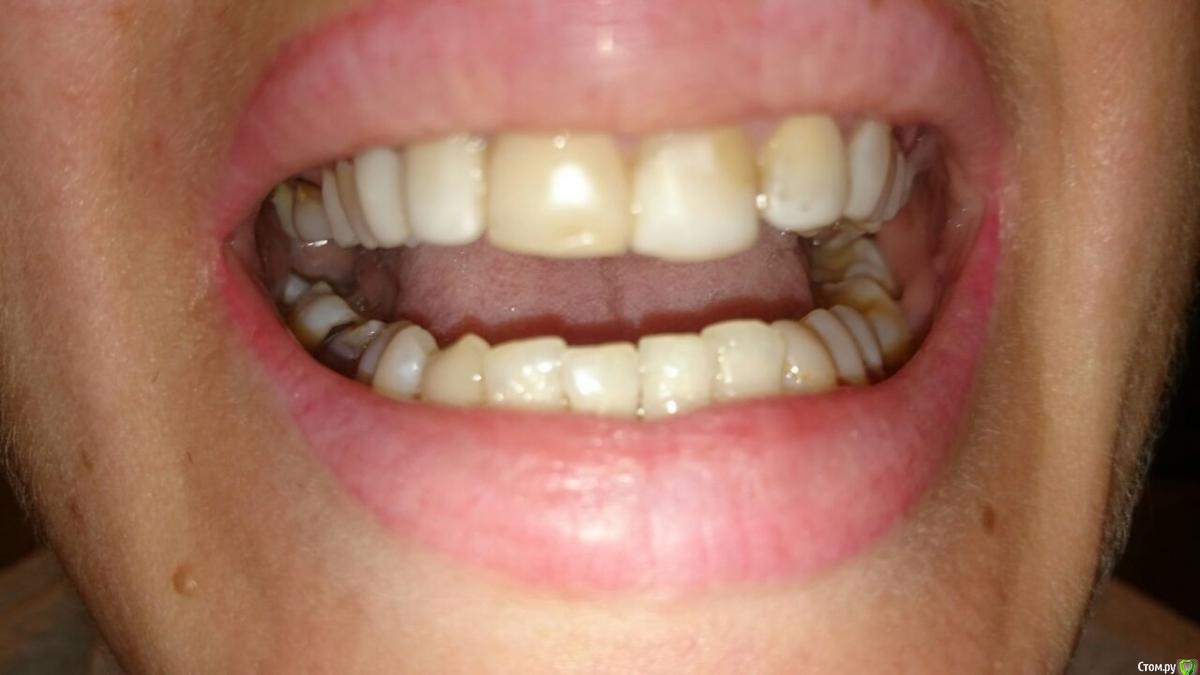

Валерьич Опубликовано 24 сентября, 2016 Поделиться Опубликовано 24 сентября, 2016 Добрый день. Снимок моей супруги ходившей на прием сегодня. Одно мнение хорошо,а много- лучше.Пояснение- передние сверху в винирах, которым 13 лет. Пора менять, это факт. Те что справа коренные под пломбами темные, верхний как бы амортизирует. Врач(или рвач?)- сказал что виниры надо убирать, зубы прятать под коронки. Насчитали 300 тысяч за 6 коронок . В общем мы в шоке от этой суммы, вроде в бюджетную клинику ходила и тут такое.Прошу многоуважаемое сообщество посмотреть снимок и дать план лечения. посоветовать с чего начинать если и вправду о таких суммах идет речь.Жена коронки вперед не хочет однозначно... 2 Ссылка на комментарий

Валерьич Опубликовано 24 сентября, 2016 Автор Поделиться Опубликовано 24 сентября, 2016 Сфоткали как смогли. Ссылка на комментарий

red_butler Опубликовано 25 сентября, 2016 Поделиться Опубликовано 25 сентября, 2016 Врач(или рвач?) к чему клеить ярлыки??? Жена коронки вперед не хочет однозначно... хотеть не хотеть, уже не важно, если не будет коронок на зубах, то будут на коронки на имплантах.По плану... профессиональная гигиена и затем1. удалять зубы мудрости и возможно 4.62. перелечивать 1.63. ревизия корневого канала 2.14. создания места для протезирования в области 3.6 (брекеты)5. имплантация в позицию 3.6 и возможно 4.66. протезирование вкладками и коронками 1.6 2.1, импланта/тов, фронт керамические коронки или виниры. А главное увидели мой вопрос не про лечение а стоимость. я тоже увидел... Насчитали 300 тысяч за 6 коронок . В общем мы в шоке от этой суммы, вроде в бюджетную клинику ходила и тут такое. Прошу многоуважаемое сообщество посмотреть снимок и дать план лечения. посоветовать с чего начинать если и вправду о таких суммах идет речь. 1 1 Ссылка на комментарий

DmitrySH Опубликовано 27 сентября, 2016 Поделиться Опубликовано 27 сентября, 2016 Маленькое уточнение.Тканей у зуба 21 фактически нет, соответственно коронка. Можете ее обозвать полным виниром, можно керамической реставрацией. Ссылка на комментарий